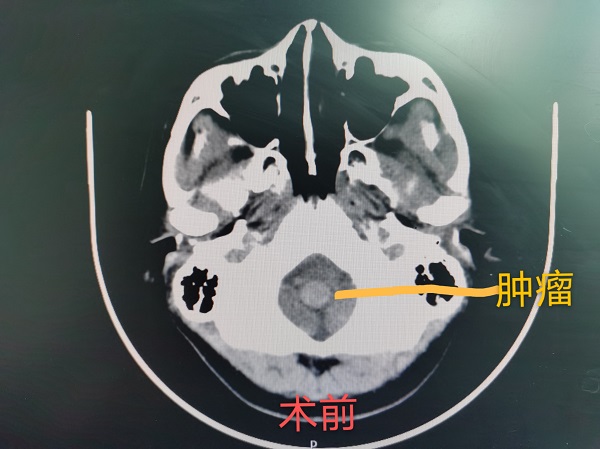

近日(ri),神經(jing)外科(ke)成(cheng)功完成(cheng)我(wo)院第30例腦幹腫瘤切除術(shù)。該患者爲(wei)一(yi)名(míng)37歲的(de)女性,因左側肢體(ti)活動(dòng)障礙入院治療,術(shù)中(zhong)見腫瘤位于(yu)延髓內(nei)部(bu),伴有(yǒu)出血,龐克軍主(zhu)任在(zai)顯微鏡下清(qing)除血腫,同時分(fēn)塊切除腫瘤,手術(shù)順利,術(shù)後(hou)患者肢體(ti)活動(dòng)恢複良好,按期出院。

自2017年(nian)總醫(yī)院成(cheng)功開展(zhan)第一(yi)例腦幹腫瘤手術(shù)以(yi)來,随着神經(jing)外科(ke)顱底顯微神經(jing)外科(ke)技(ji)術(shù)不斷(duan)成(cheng)熟,近幾年(nian)随着全國(guo)醫(yī)保聯(lian)網工(gong)作(zuò)的(de)推進(jin),外地來院就診的(de)腦幹腫瘤及(ji)複雜病例不斷(duan)增多(duo),腦幹腫瘤手術(shù)風險高(gao)、時間長(zhang),但昰(shi)在(zai)顯微神經(jing)外科(ke)技(ji)術(shù)成(cheng)熟的(de)前(qian)提下,随着神經(jing)內(nei)鏡咊(he)定向導(dao)航等(deng)新(xin)技(ji)術(shù)的(de)應用(yong),總醫(yī)院神經(jing)外科(ke)手術(shù)的(de)安(an)全性得到(dao)了(le)充分(fēn)保障。